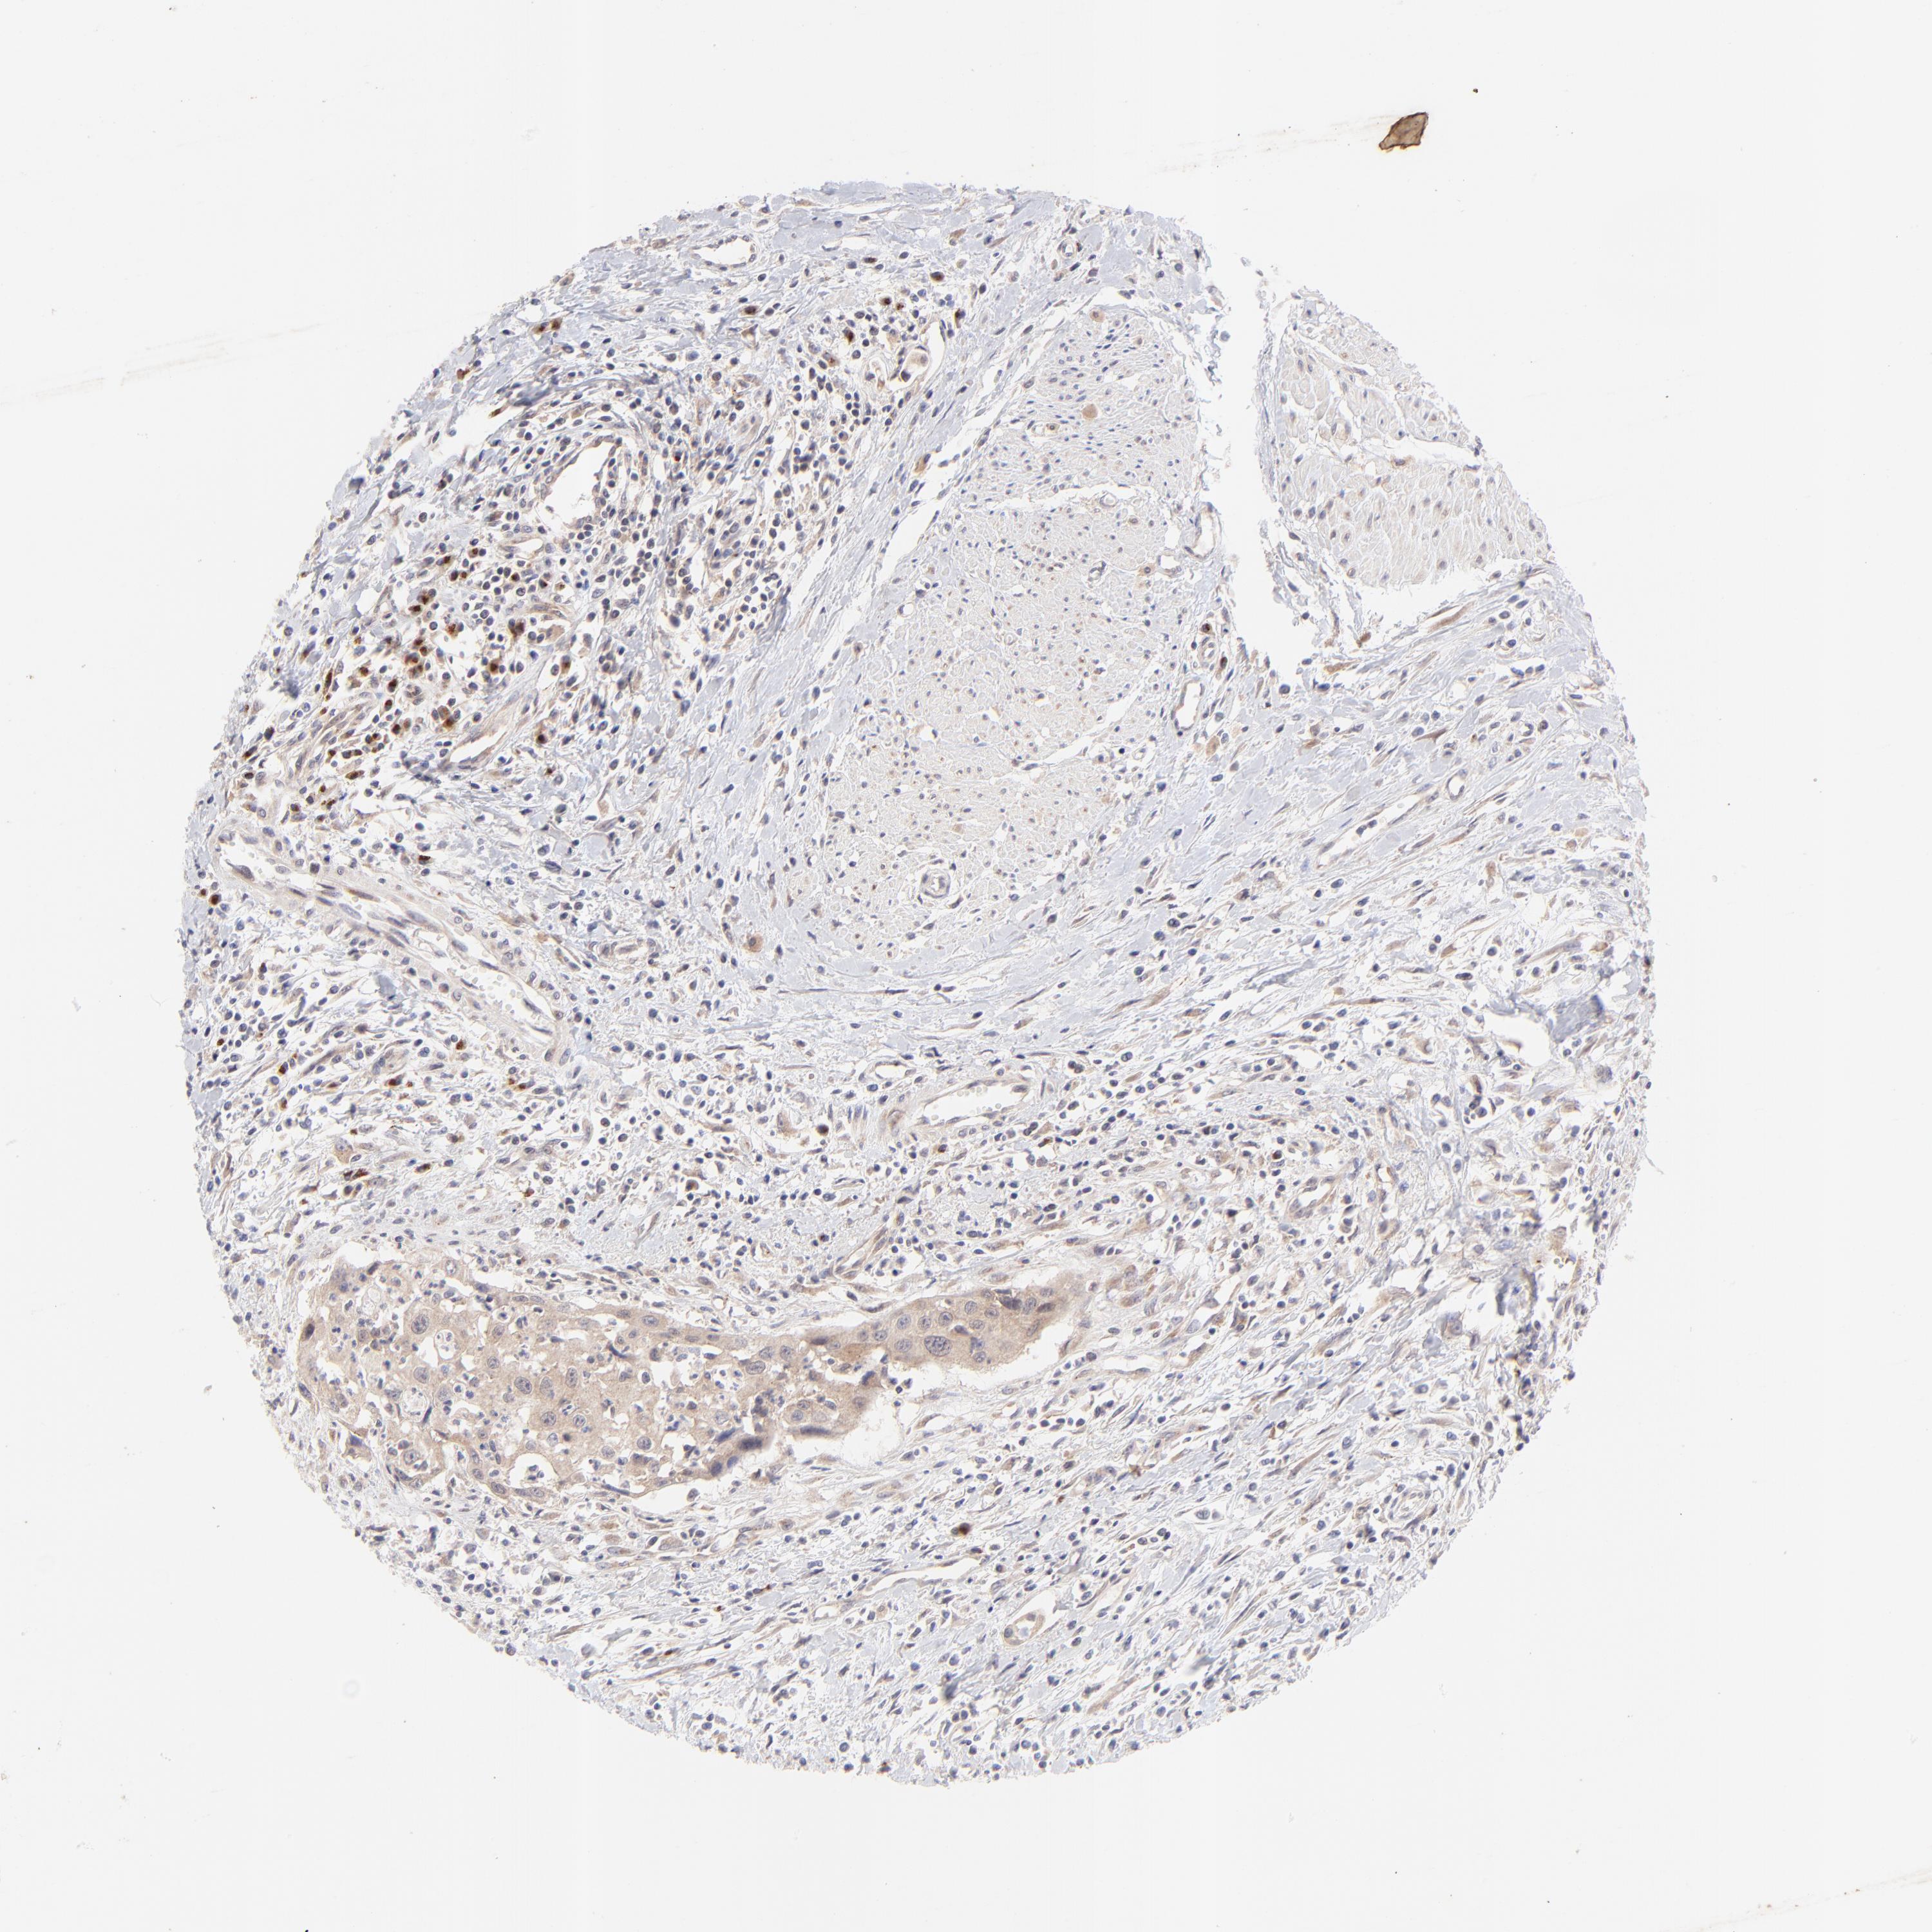

UROTHELIAL CANCER - Protein expressioni

A mouse-over function shows sample information and annotation data. Click on an image to view it in a full screen mode. Samples can be filtered based on level of antibody staining by selecting one or several of the following categories: high, medium, low and not detected. The assay and annotation is described here.

Note that samples used for immunohistochemistry by the Human Protein Atlas do not correspond to samples in the TCGA dataset.

Antibody stainingi

Antibody staining in the annotated cell types in the current human tissue is reported as not detected, low, medium, or high, based on conventional immunohistochemistry profiling in selected tissues. This score is based on the combination of the staining intensity and fraction of stained cells.

Each image is clickable and will lead to virtual microscopy that enables deeper exploration of all samples and also displays staining intensity scores, fraction scores and subcellular localization as well as patient and tissue information for each sample.

Antibody HPA003180

Staining

High

Medium

Low

Not detected

Intensity

Strong

Moderate

Weak

Negative

Quantity

>75%

75%-25%

<25%

None

Location

Nuclear

Cytoplasmic/membranous

Cytoplasmic/membranous,nuclear

Urothelial carcinoma, High grade

Urothelial carcinoma, Low grade